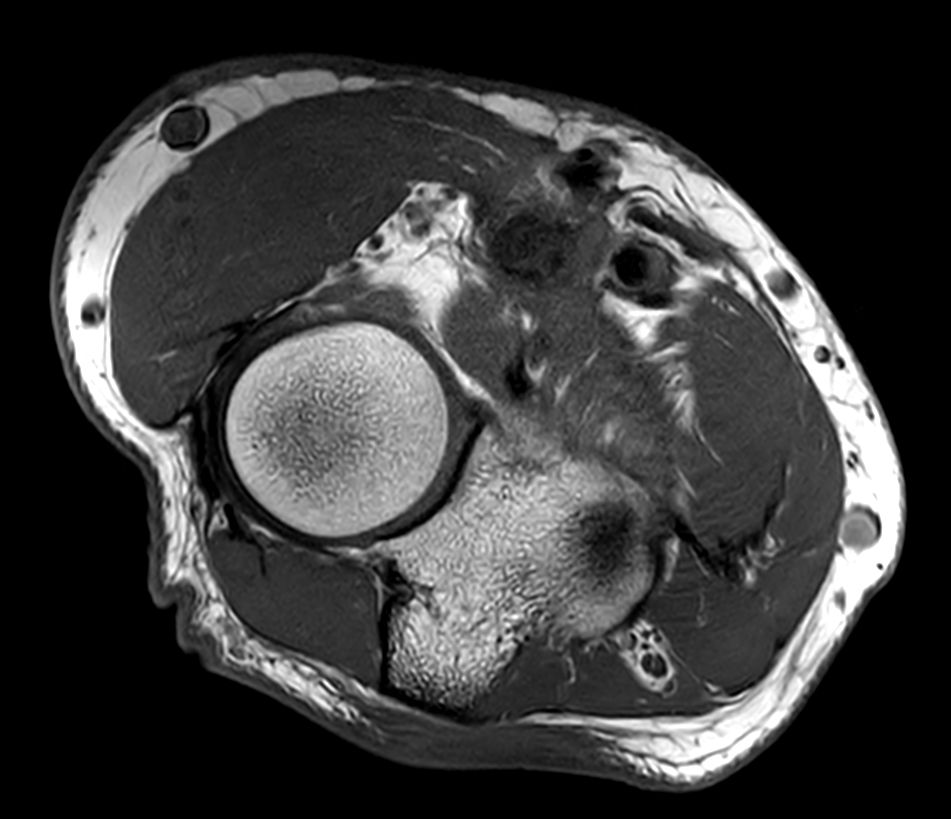

Routine Elbow

Routine imaging of the Elbow with the dS Small Extremity 8ch coil. MultiVane XD is used to deliver high resolution diagnostic images even in the case of patient motion. Compressed is used to speed up the entire exam with virtually equal image quality1.

PDw TSE FatSat Compressed SENSE